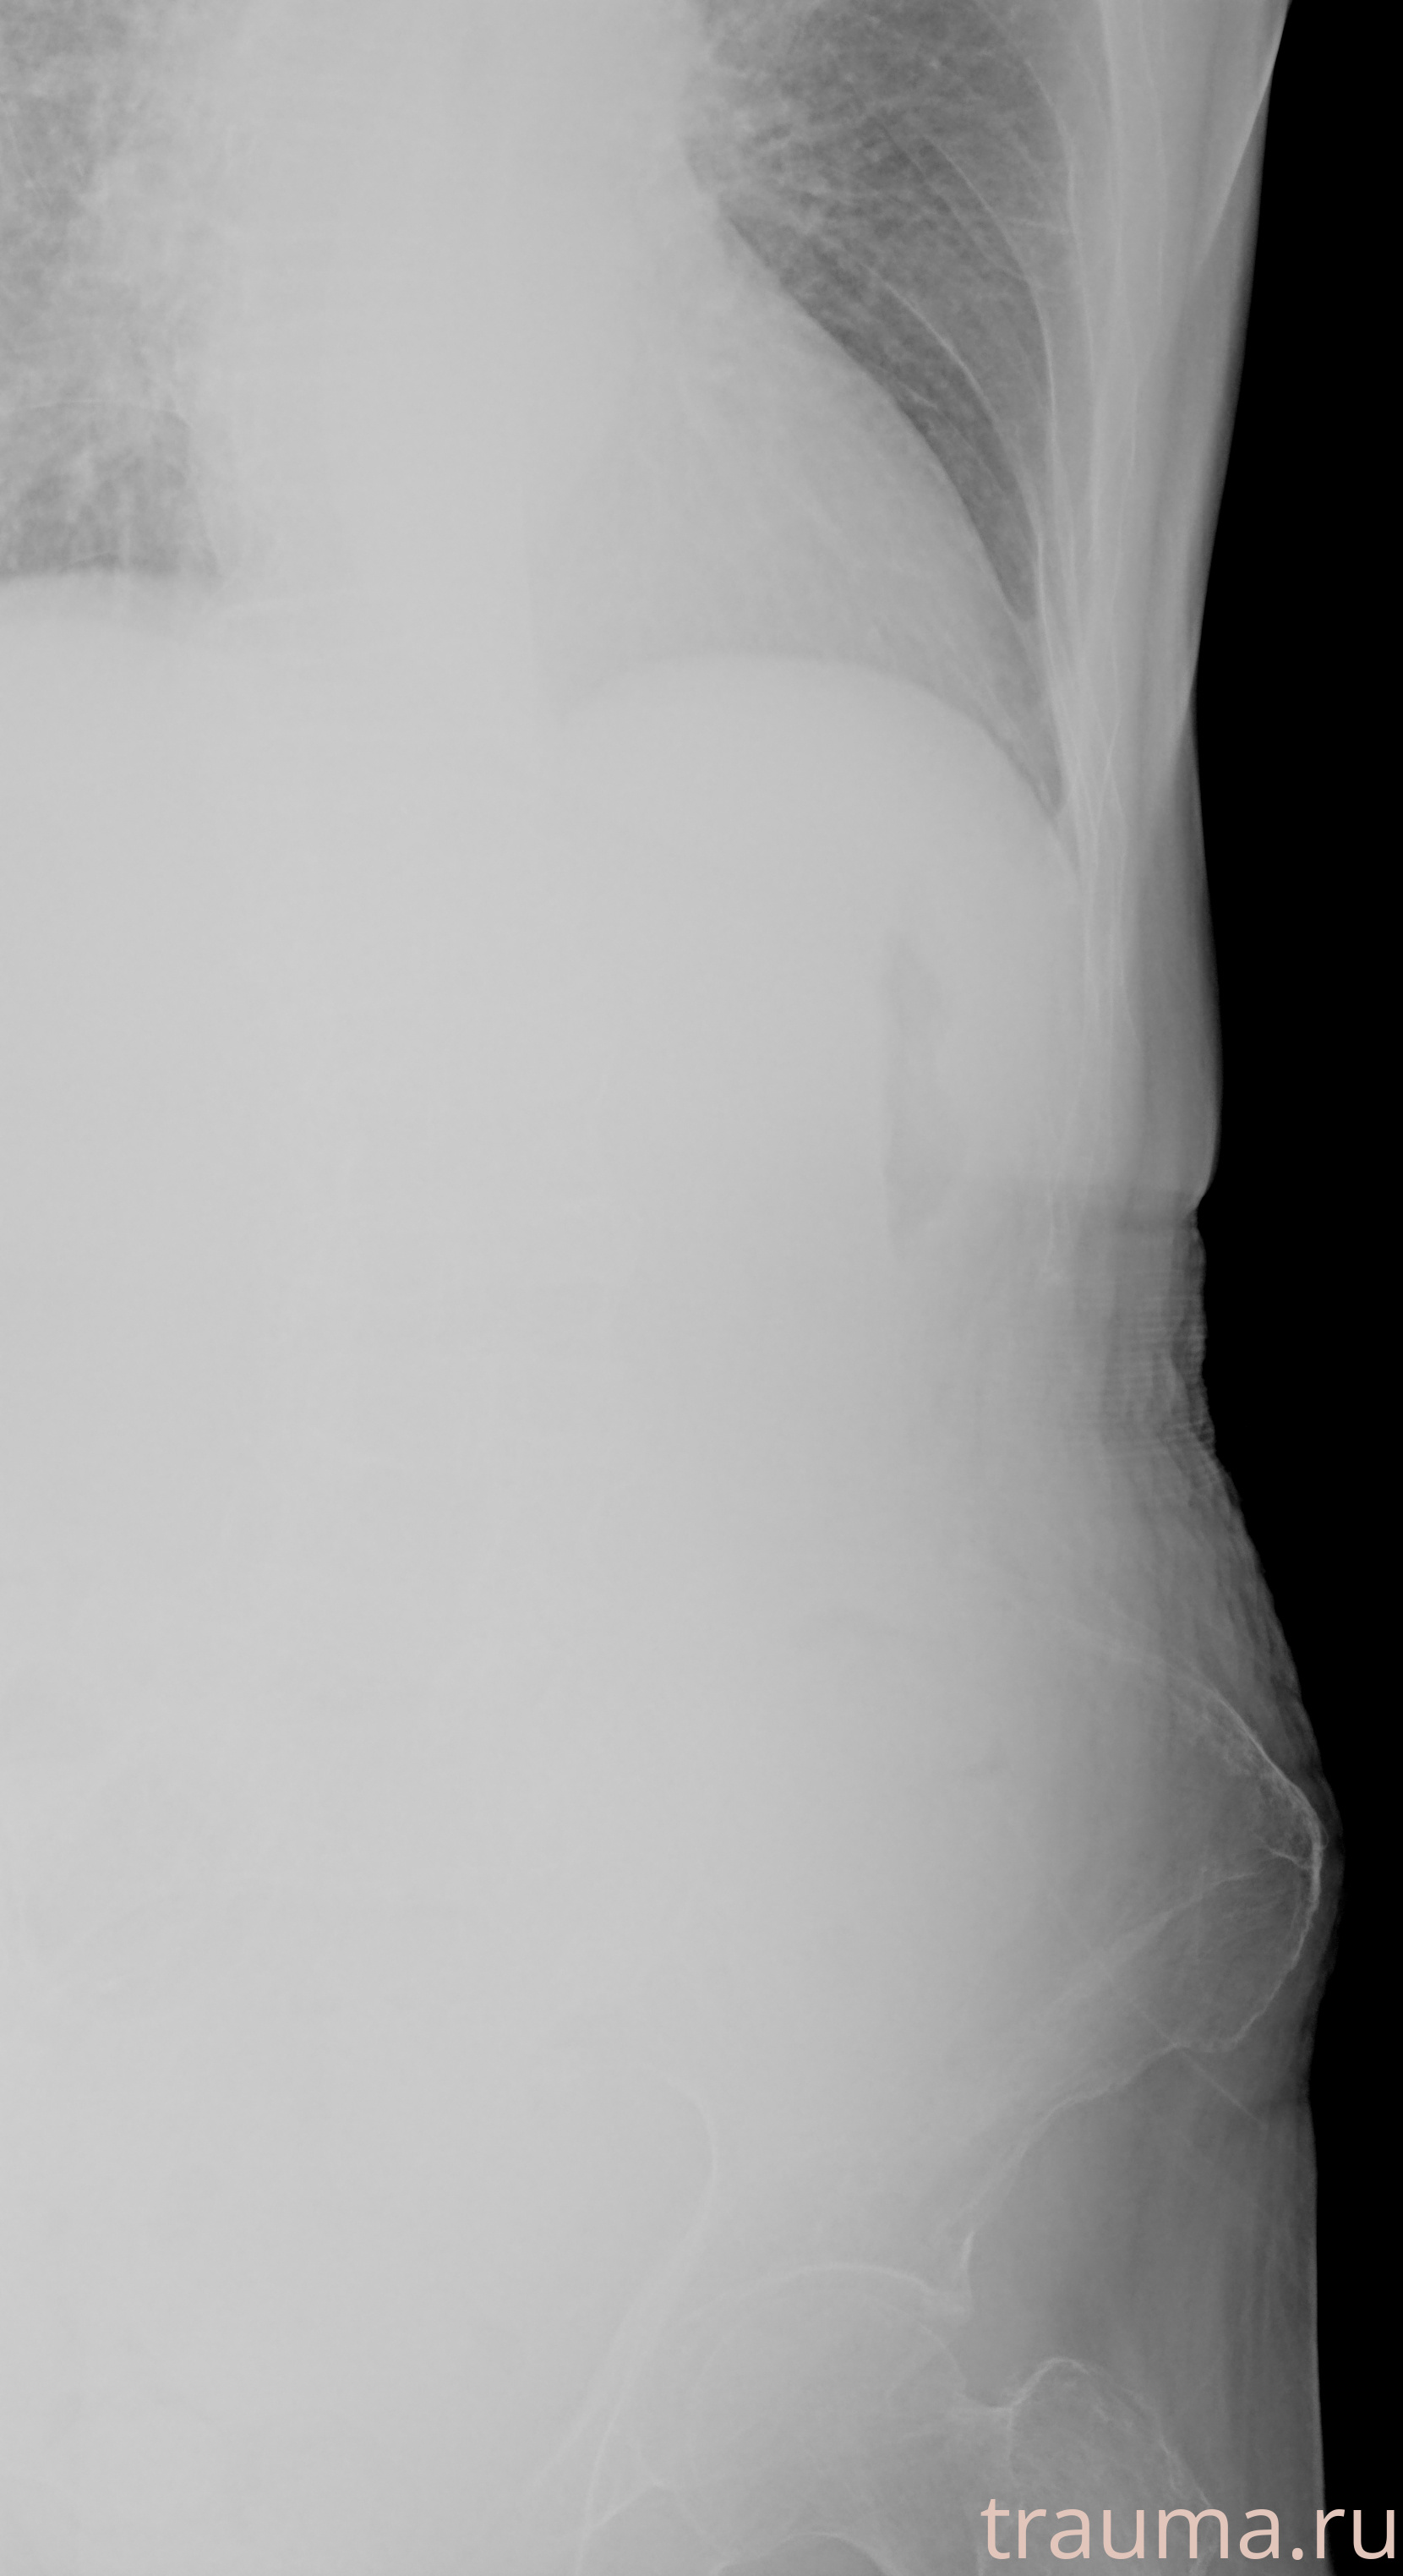

Рентгенограммы

Рентген на дому: по вашему адресу приезжает врач-рентгенолог, травматолог-ортопед с мобильным рентгеновским аппаратом, проводит диагностику травмы или заболевания, делает необходимые рентгенограммы, дает рекомендации по дальнейшему лечению. Получить качественные снимки в домашних условиях возможно благодаря уникальной методике, разработанной МосРентген Центром для института  Склифосовского

при переломе шейки бедра и пневмонии от компании МосРентген Центр - партнера Института имени Склифосовского